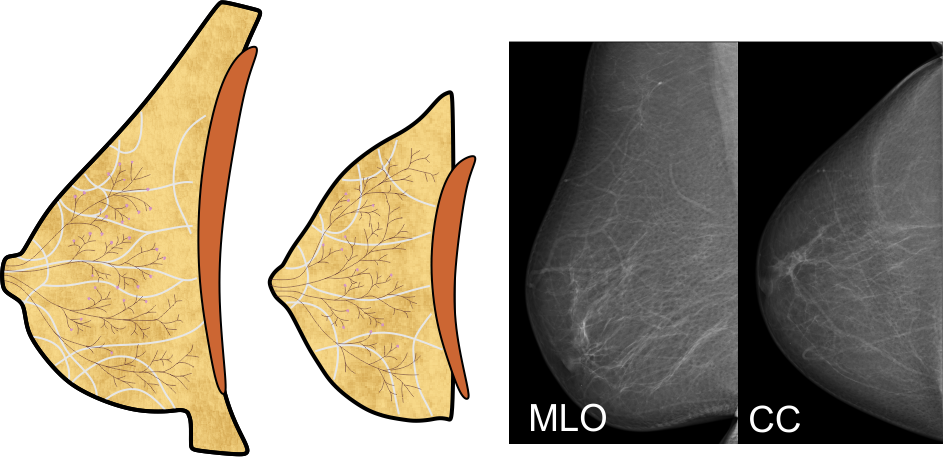

Die weibliche Brust besteht in Hauptsache aus den vier Komponenten Fettgewebe, Bindegewebe, und den Milchgängen und Milchdrüsenläppchen, die zusammen die Brustdrüse bilden:

Das Fettgewebe gibt der Brust ihre Form, das Bindegewebe durchzieht die Brust in gewölbten, fächerartigen Bahnen und verleiht ihr Stabilität. Die Milchgänge leiten die Milch zur Brustwarze, und in den Drüsenläppchen wird die Milch gebildet; die rotbraune Fläche in den obigen Abbildungen symbolisiert den Brustmuskel.

Aufbau der Brustdrüse

Die Brustdrüse gliedert sich in 10 bis 16 Drüsenlappen, im obigen Bild sind vier davon dargestellt. Ein Drüsenlappen lässt sich gut mit einem Baum vergleichen:

Der Stamm des Baums endet in der Brustwarze, seine Äste und Zweige entsprechen den Milchgängen, und die Blätter bilden die Milchdrüsenläppchen. Die 'Blätter' sind allerdings nicht flach, sondern sehen eher wie Himbeeren mit einem kurzen Stiel aus - hier eine Sicht durch das Mikroskop:

Der Stamm des Baums endet in der Brustwarze, seine Äste und Zweige entsprechen den Milchgängen, und die Blätter bilden die Milchdrüsenläppchen. Die 'Blätter' sind allerdings nicht flach, sondern sehen eher wie Himbeeren mit einem kurzen Stiel aus - hier eine Sicht durch das Mikroskop:

Mit freundlicher Genehmigung von Prof. László Tabár

Aufbau der Brust

Die vier oben genannten Gewebearten sind in ihren Anteilen in jeder Brust individuell angelegt. Die meisten Frauen haben eine ausgewogene Verteilung, bei manchen kann jedoch eine bestimmte Gewebeart überwiegen. Dazu verändert sich die Brust mit zunehmendem Alter, die Milchgänge und das Bindegewebe werden vor allem nach dem Wechsel dünner, die 'Blätter' des Baums 'verwelken' - die Drüsenläppchen schrumpfen also, und der Fettgewebeanteil wird größer. Üblicherweise entwickeln sich diese Veränderungen von innen nach außen, und von unten nach oben.

Tumore können aus allen vier Gewebearten hervorgehen. Tumore des Binde- und Fettgewebes sind zumeist gutartig, Tumore der Milchgänge und Drüsenläppchen sind meist bösartig. Diese Tumore werden üblicherweise als Brustkrebs bezeichnet.